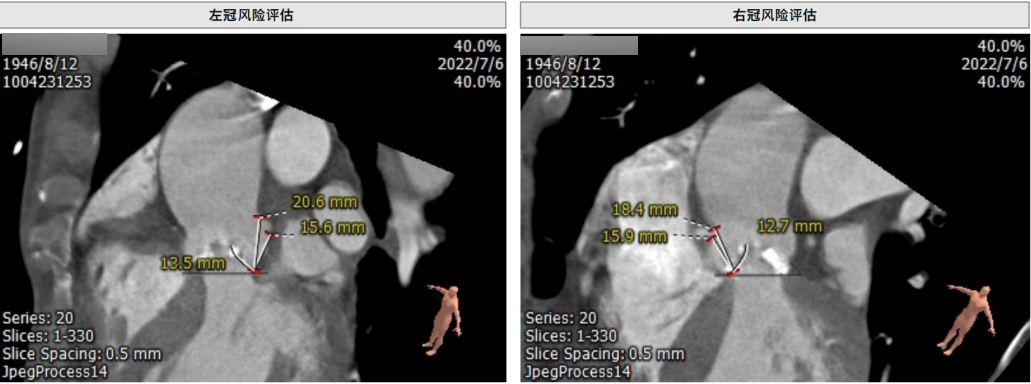

主动脉根部CT测量

瓣环平均直径:21.5mm;LOVT平均直径:19.8mm

左冠开口高度:13.5mm;右冠开口高度:12.7mm

主动脉瓣钙化分布情况

入路情况

血管入路严重迂曲